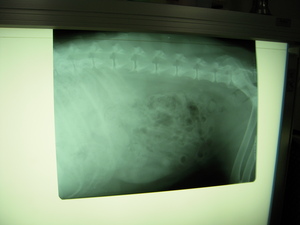

ミッフィの通院日。

レントゲンと血液検査をしました。

特に問題なし^^

おなかの中には

ごはんの痕跡が、、、、、